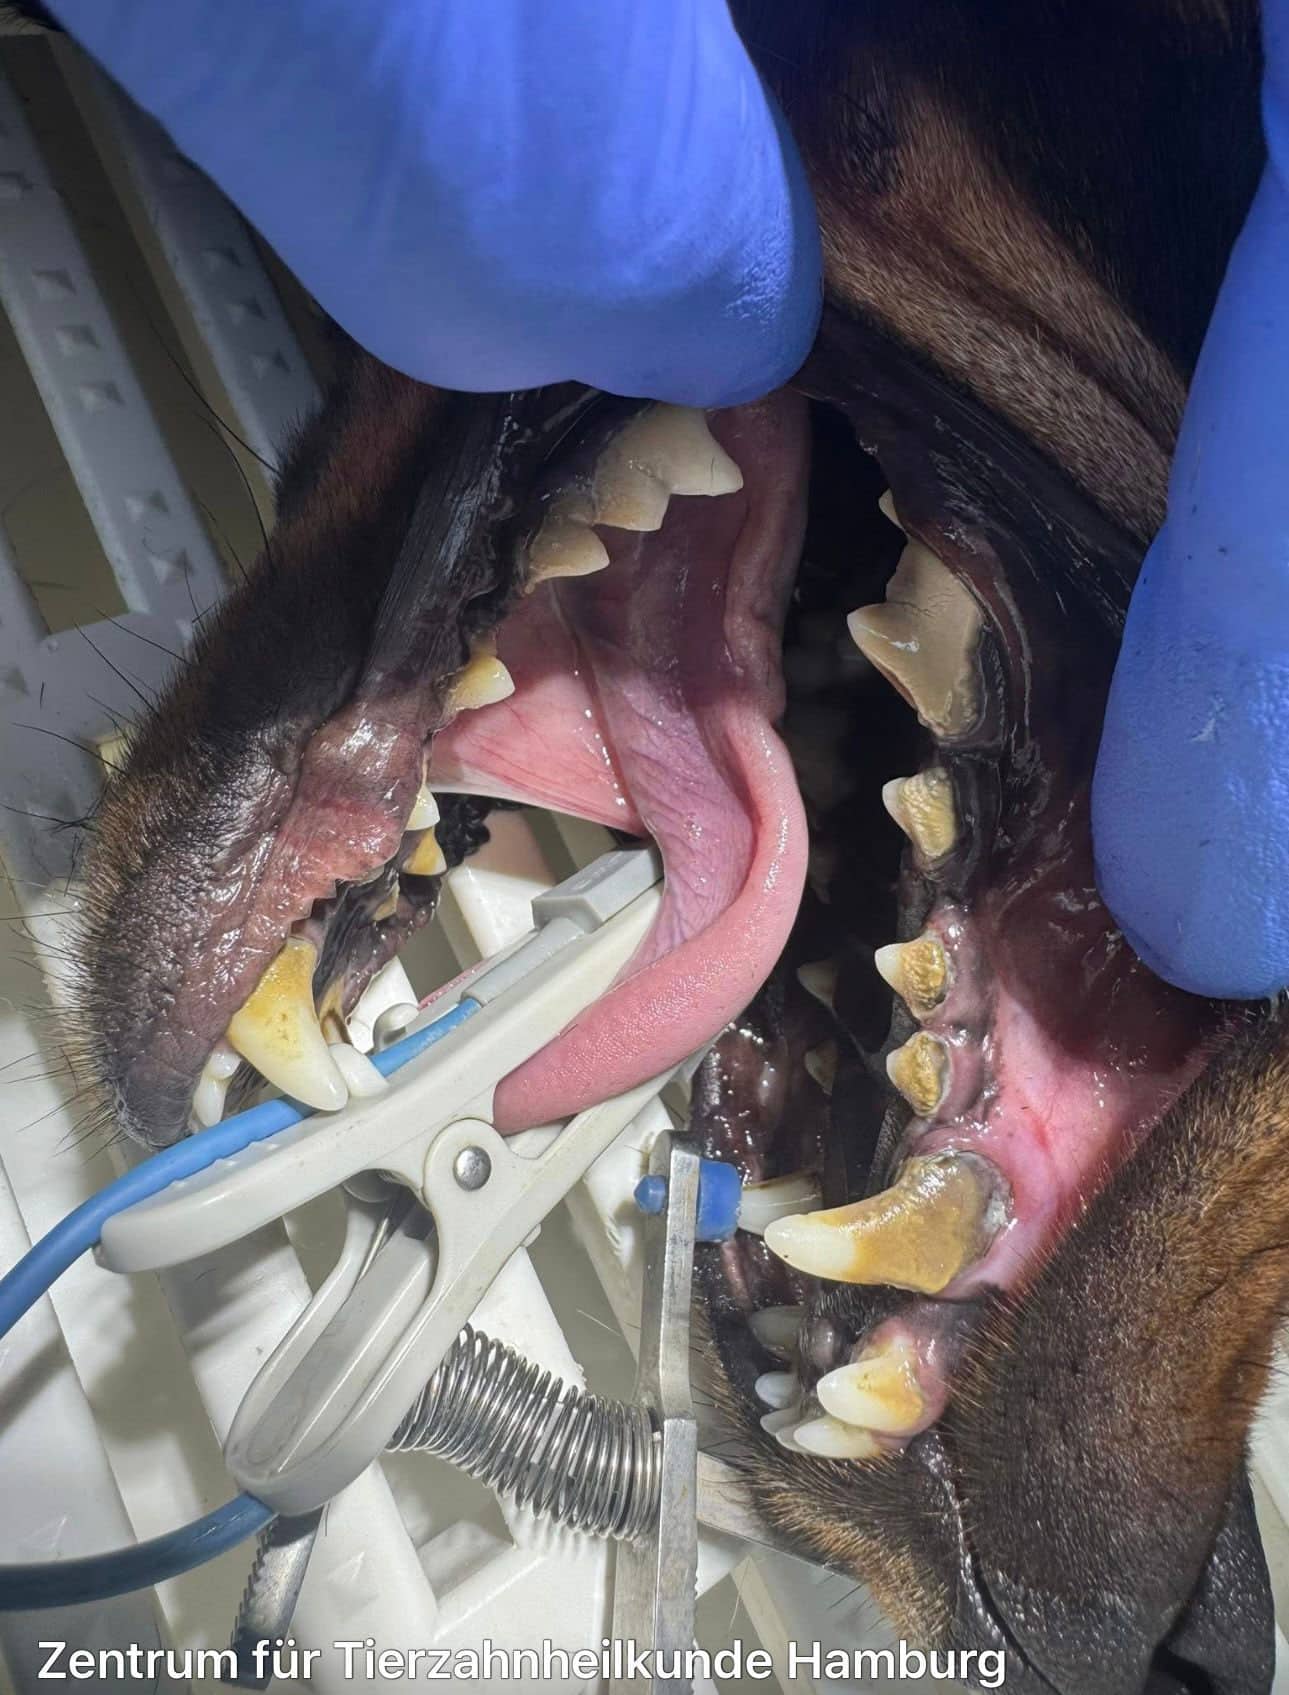

Beispielfotos unserer Patienten

Vorher

Das sollten Sie behandeln lassen!

Nachher

Wir entfernen den Zahnstein vollständig und professionell